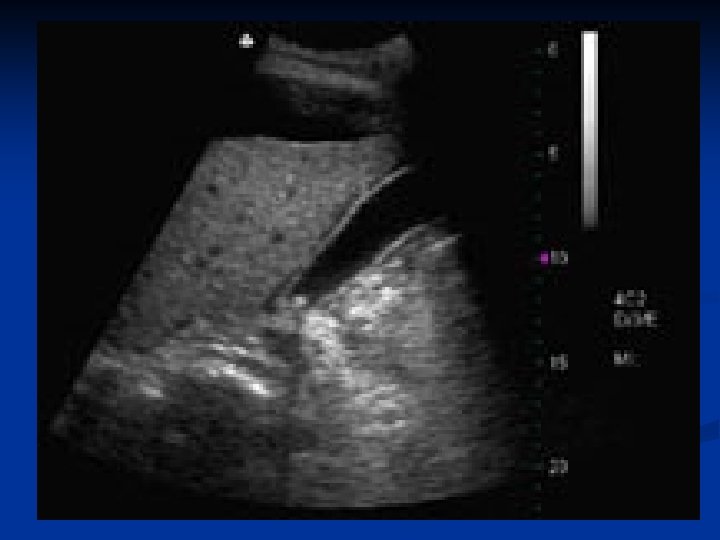

Ангиография селезеночной артерии до эмболизации

Вид после эмболизации селезеночной артерии